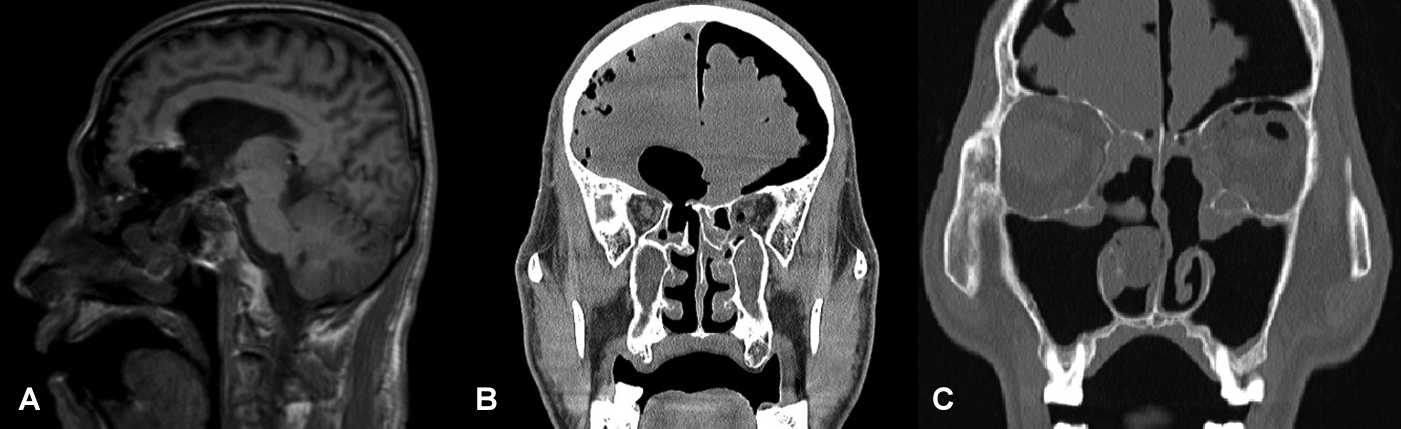

A 65-year-old male patient presented with recurring CSF leakage. Formerly in good health, aside from asthma, initial CSF leakage occurred presumably after bilateral endoscopic sinus surgery and septoturbinoplasty at local hospital. Subsequently, due to an altered conscious status after sinus surgery, he was transferred to another tertiary hospital. Magnetic resonance and computed tomography imaging revealed a skull base defect in right ethmoid roof defect, tension pneumocephalus, brain parenchymal damage, and bilateral lamina papyracea (LP) defect (Fig. 1).

Fig. 1.

Initial (post-traumatic) images. A: T1-weighted MRI revealing a defect connected to the ventricles. B: CT findings indicating a right ethmoid roof defect and tension pneumocephalus. C: Left lamina papyracea defect.